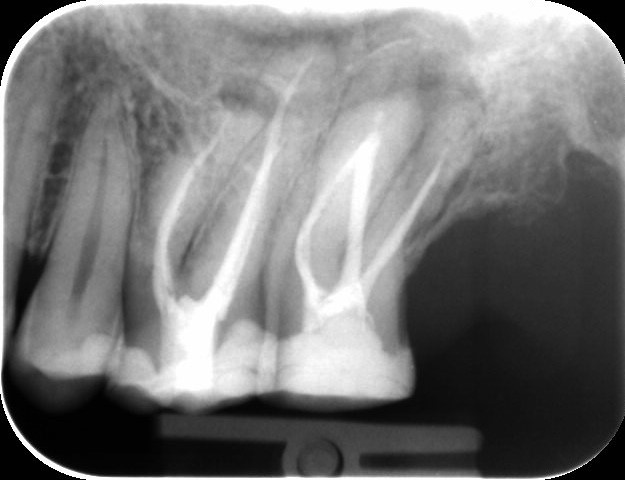

wie kan een Xray lezen? Hierbij een foto van 2 van mijn bovenste kiezen links boven. Is op beide ooit een WKB uitgevoerd. Wie ziet er iets aan?

bij beide kiezen zitten (opnieuw) zwartingen. Hoe lang geleden zijn ze behandeld? wellicht is eea met herbehandelingen oplosbaar. Hier en daar is wellicht ook wat meer te bereiken met de modernere technieken heden ten dage.